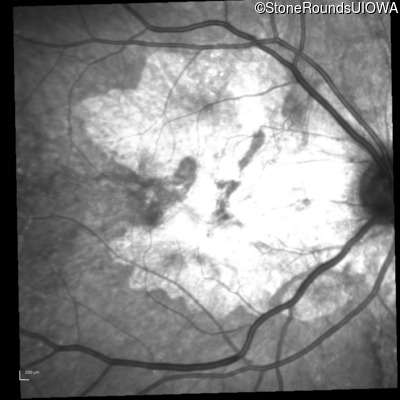

Fluorescein Angiography - Left - 20/20 -2

Exemplar